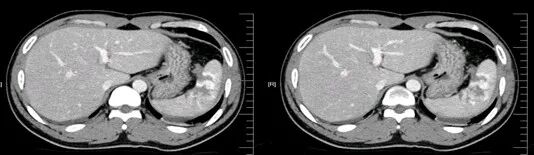

胃癌

进展期胃癌CT检查有利于观察病变的侵犯范围和淋巴结转移情况

早期胃癌多数病人无明显症状,少数人有恶心、呕吐或是类似溃疡病的上消化道症状。疼痛与体重减轻是进展期胃癌最常见的临床症状。病人常有较为明确的上消化道症状,如上腹不适、进食后饱胀,随着病情进展上腹疼痛加重,食欲下降、乏力。

根据肿瘤的部位不同,也有其特殊表现。

贲门胃底癌可有胸骨后疼痛和进行性吞咽困难;幽门附近的胃癌有幽门梗阻表现;肿瘤破坏血管后可有呕血、黑便等消化道出血症状。

腹部持续疼痛常提示肿瘤扩展超出胃壁,如锁骨上淋巴结肿大、腹水、黄疸、腹部包块、直肠前凹扪及肿块等。

晚期胃癌病人常可出现贫血、消瘦、营养不良甚至恶病质等表现。

胃癌的扩散和转移有以下途径:

1.直接浸润

2.血行转移

3.腹膜种植转移:女性病人胃癌可发生卵巢转移性肿瘤。

4.淋巴转移

气腹管怎么接肠梗阻、肠套叠、气腹、肝挫伤、脾挫伤、肾挫伤、胰腺损伤、食管癌、胃肠肿瘤_https://www.jmylbn.com_新闻资讯_第40张

气腹管怎么接肠梗阻、肠套叠、气腹、肝挫伤、脾挫伤、肾挫伤、胰腺损伤、食管癌、胃肠肿瘤_https://www.jmylbn.com_新闻资讯_第41张

气腹管怎么接肠梗阻、肠套叠、气腹、肝挫伤、脾挫伤、肾挫伤、胰腺损伤、食管癌、胃肠肿瘤_https://www.jmylbn.com_新闻资讯_第42张

幽门癌